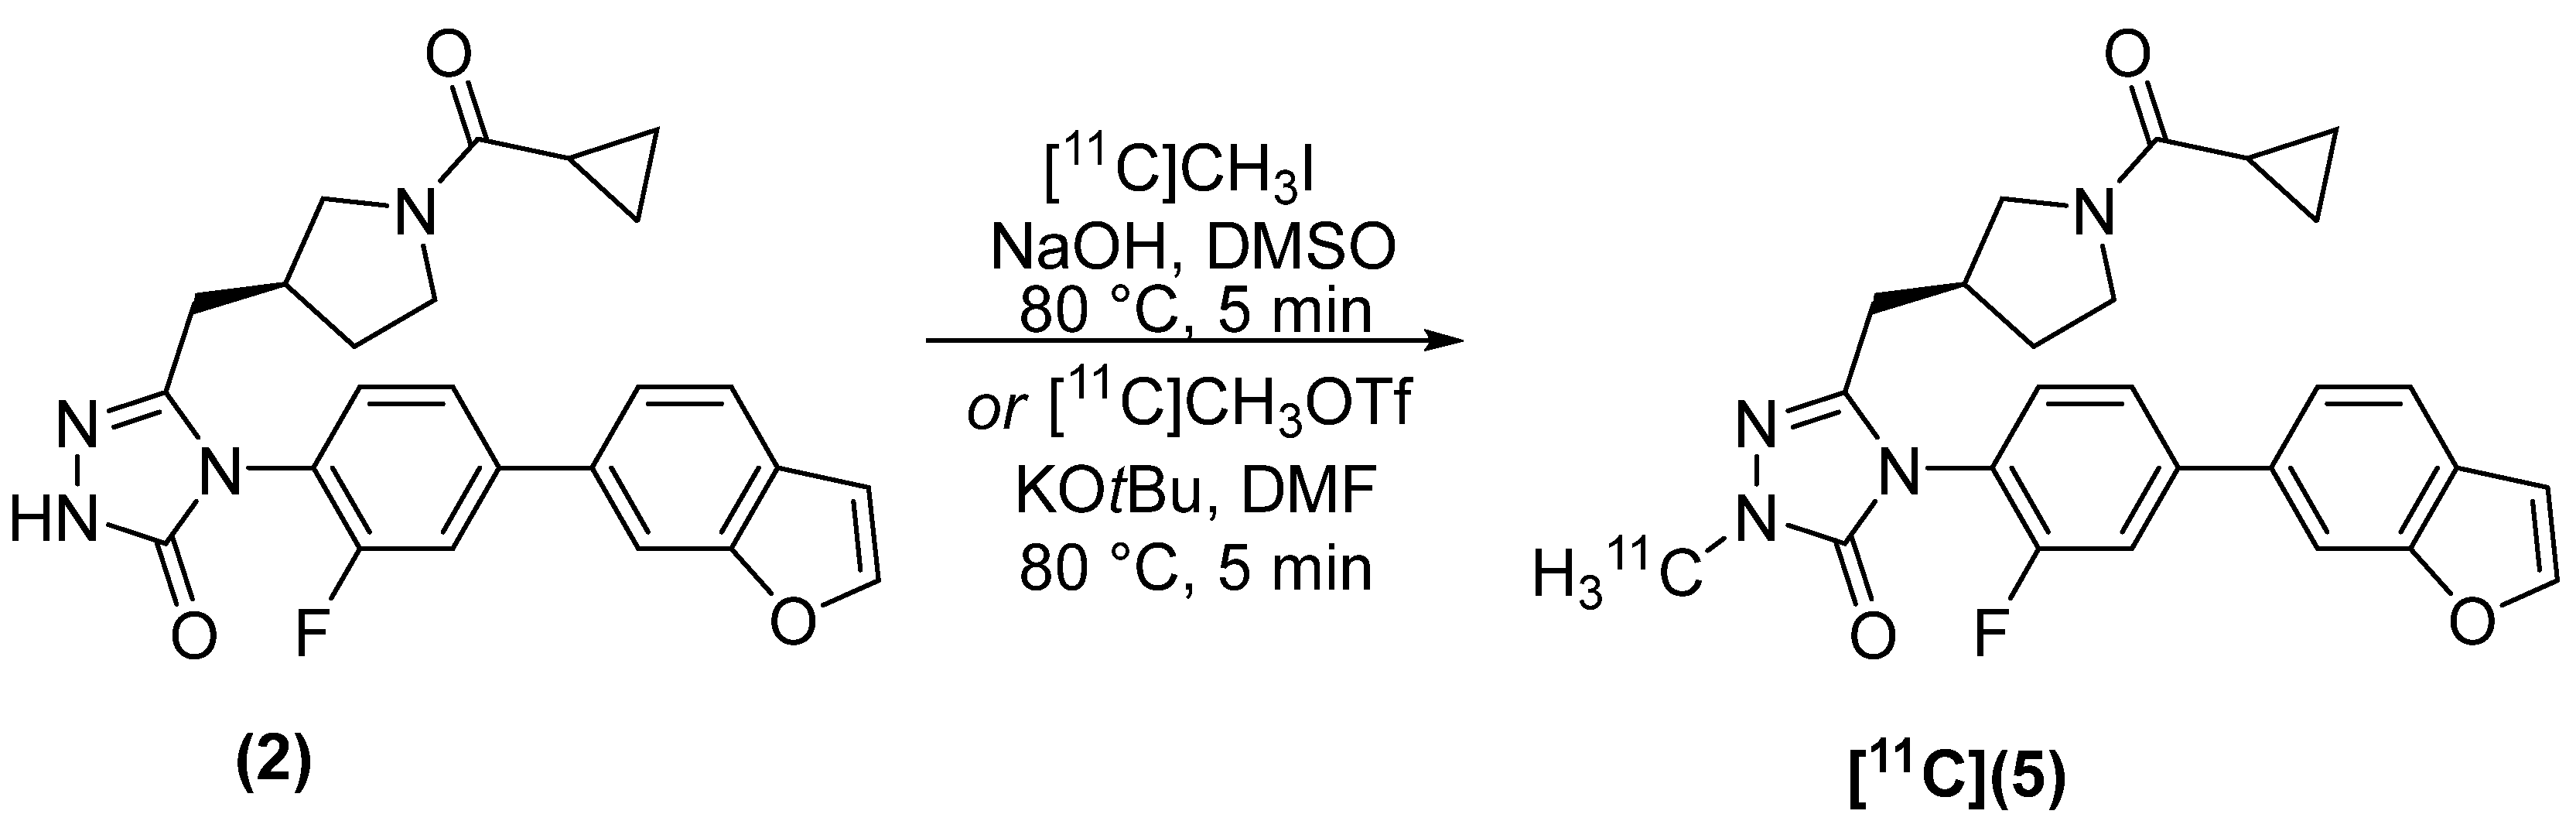

2.2. Radiosynthesis

4.2.2. (S)-4-(4-(benzofuran-6-yl)-2-fluorophenyl)-5-((1-(cyclopropanecarbonyl)pyrrolidin-3-yl)methyl)-2-[methyl-11C]-2,4-dihydro-3H-1,2,4-triazol-3-one [11C]5